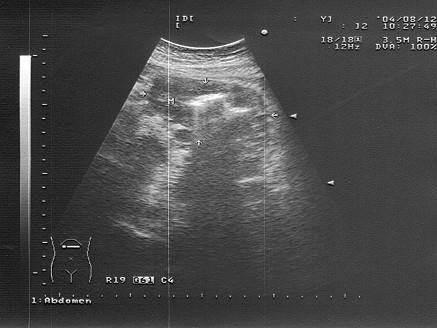

问题 男,67岁,呕血,有胃溃疡病史,治疗后可缓解。根据超声声像图诊断为?(?)

选项 A.结肠肝曲癌 B.肝癌 C.胃癌 D.腹膜后肿块 E.胃溃疡

答案 C